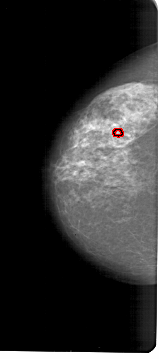

A_1632_1.RIGHT_MLO

RIGHT_CC LINES 5866 PIXELS_PER_LINE 2971 BITS_PER_PIXEL 12 RESOLUTION 43.5 NON_OVERLAY

RIGHT_MLO LINES 6646 PIXELS_PER_LINE 3181 BITS_PER_PIXEL 12 RESOLUTION 43.5 NON_OVERLAY